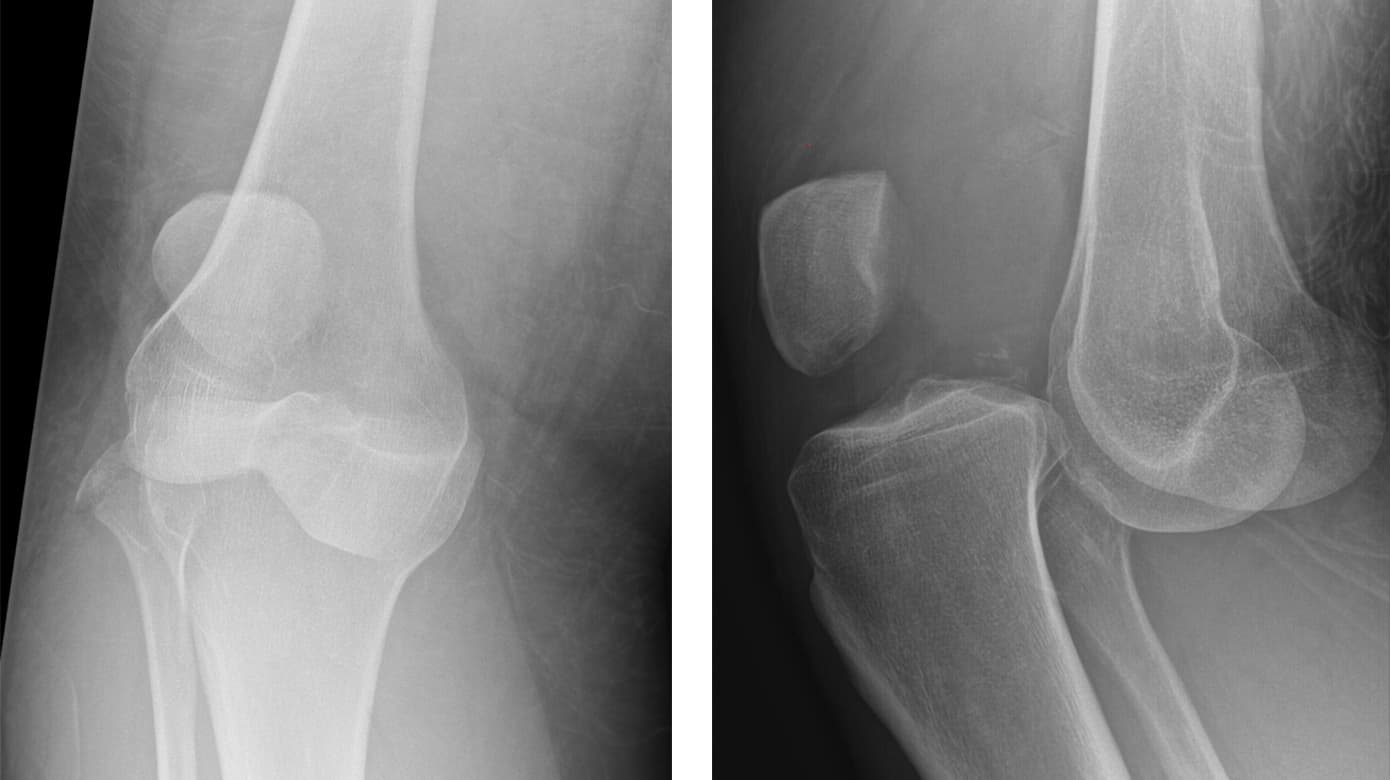

Behandling af knæluksation

Knædislokationer (KD) er relativt sjældne, men de frembyder meget komplekse problemstillinger, som behandlingsmæssigt skal kunne trække på traumatologer, idrætskirurger, neurokirurger og karkirurger samt specialiseret genoptræning. Behandlingen af KD er af denne grund ifølge specialeplanen samlet på fire afdelinger i Denmark, nemlig i Aarhus, Aalborg, Odense og Bispebjerg (i København).